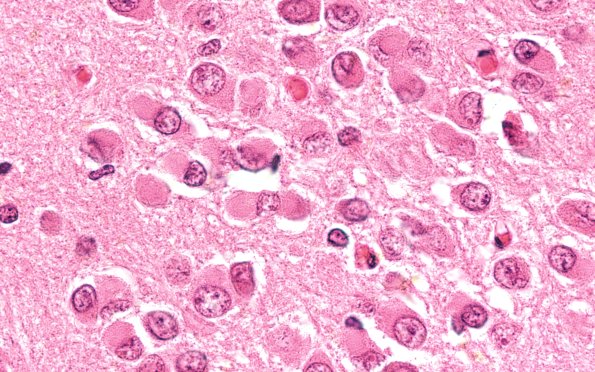

Pick Disease

8B2 Pick Dz (Case 8) HC 100X 2

Multiple neurons have Pick bodies in the dentate gyrus of the hippocampus. (H&E)